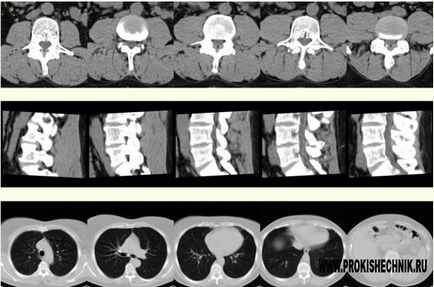

A működési elve a komputertomográfia

Abban az esetben, CT technika vizsgált részét a beteg rétegek befolyásolja gerenda X-sugárzás, amelyet elküldött a speciális berendezésben. Mivel a különböző sűrűségű szövetek-sugarak felszívódik eltérően őket, hogy rögzítse speciális eszközökkel. Ezek az adatok feldolgozására, majd adja a képet rétegződés metszeteken, azaz fizikai állapotát.

CT informatívabb, hogy

- Diagnózis A keringési rendellenességek, agyi daganatok;

- Veszteségek fogak, arckoponya, a pajzsmirigy és a mellékpajzsmirigy és a pofák;

- Sérülések a koponyacsontok, az agy és a koponyán belüli vérömlenyek;

- Elváltozások a halántékcsont, orrmelléküregek és a koponya bázis;

- Diagnózis otitis, sinusitis és a piramisok halántékcsont;

- Szinte az összes kórkép esetében a has;

- Atheroszklerotikus érrendszeri elváltozások és aneurizma;

- Tuberkulózis kutatás, tüdőrák, tüdőgyulladás és más szokatlan a mellkas;

- Betegségek gerinc (porckorongsérv, csontritkulás, scoliosis, stb);

- Megfigyelések a fém implantátumok, csont sérülések és betegségek.